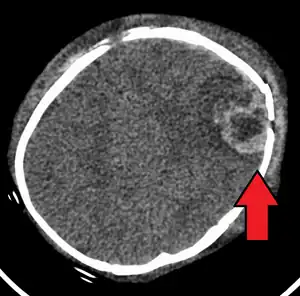

| An intraparenchymal bleed with overlying skull fracture from abusive head trauma | |

Characteristic injuries associated with AHT include retinal bleeds, multiple fractures of the long bones, and subdural hematomas (bleeding in the brain).[5] These signs have evolved through the years as the accepted and recognized signs of child abuse. Medical professionals strongly suspect shaking as the cause of injuries when a young child presents with retinal bleed, fractures, soft tissue injuries or subdural hematoma, that cannot be explained by accidental trauma or other medical conditions.[6]

AHT may be misdiagnosed, underdiagnosed, and overdiagnosed,[26] and caregivers may lie or be unaware of the mechanism of injury.[11] Commonly, there are no externally visible signs of the condition.[11] Examination by an experienced ophthalmologist is often critical in diagnosing shaken baby syndrome, as particular forms of ocular bleeding are quite characteristic.[27] Magnetic resonance imaging may also depict retinal bleeding;[28] this may occasionally be useful if an ophthalmologist examination is delayed or unavailable. Conditions that are often excluded by clinicians include hydrocephalus, sudden infant death syndrome (SIDS), seizure disorders, and infectious or congenital diseases like meningitis and metabolic disorders.[29][30] CT scanning and magnetic resonance imaging are used to diagnose the condition.[11] Conditions that may accompany AHT include bone fractures, injury to the cervical spine (in the neck), retinal bleeding, cerebral bleed or atrophy, hydrocephalus, and papilledema (swelling of the optic disc).[12]